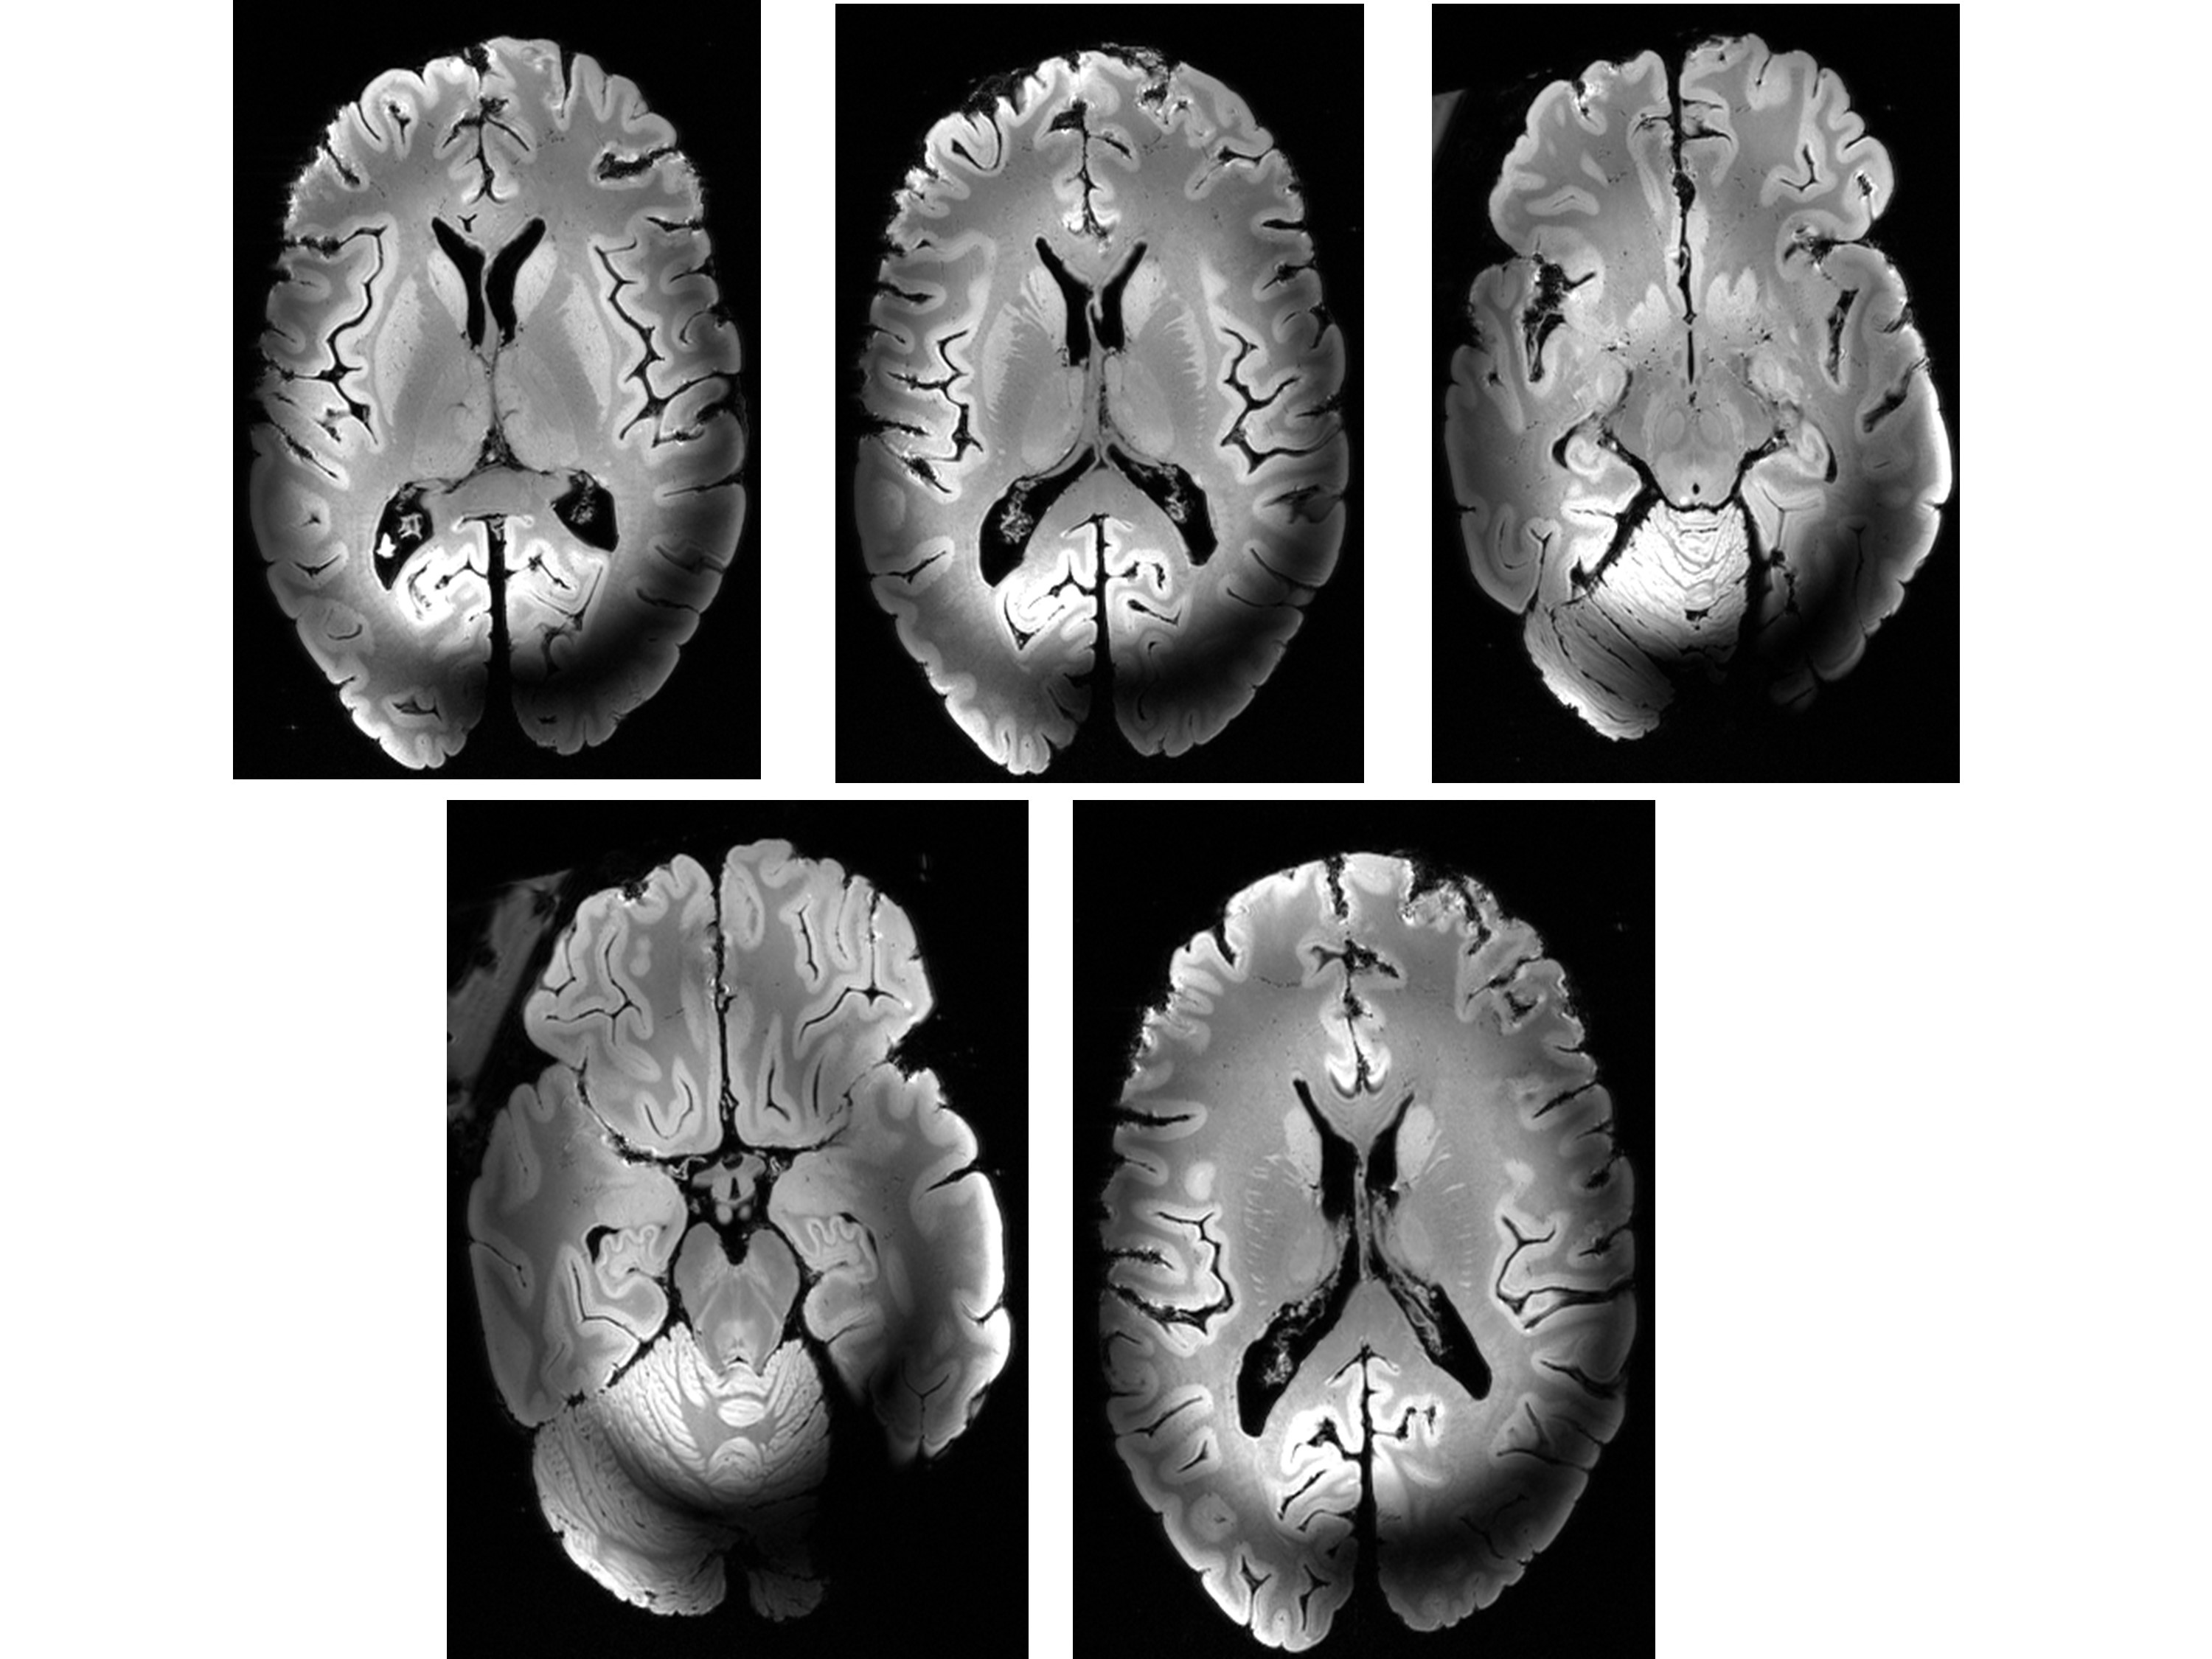

Figure 3: Ex vivo images of the human brain obtained with the Iseult 11.7T MRI scanner

Images show exquisite details, but also artifacts resulting from the inhomogeneity of the 500MHz RF field due to its shortwave length compared to the brain size (brain sample courtesy of the Museum d’Histoire Naturelle, Paris).